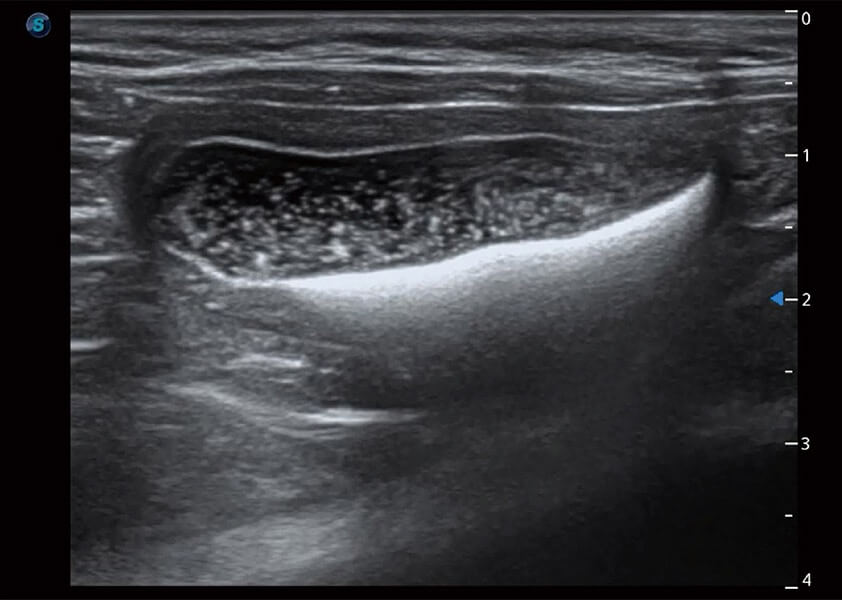

(犬)胆囊泥沙